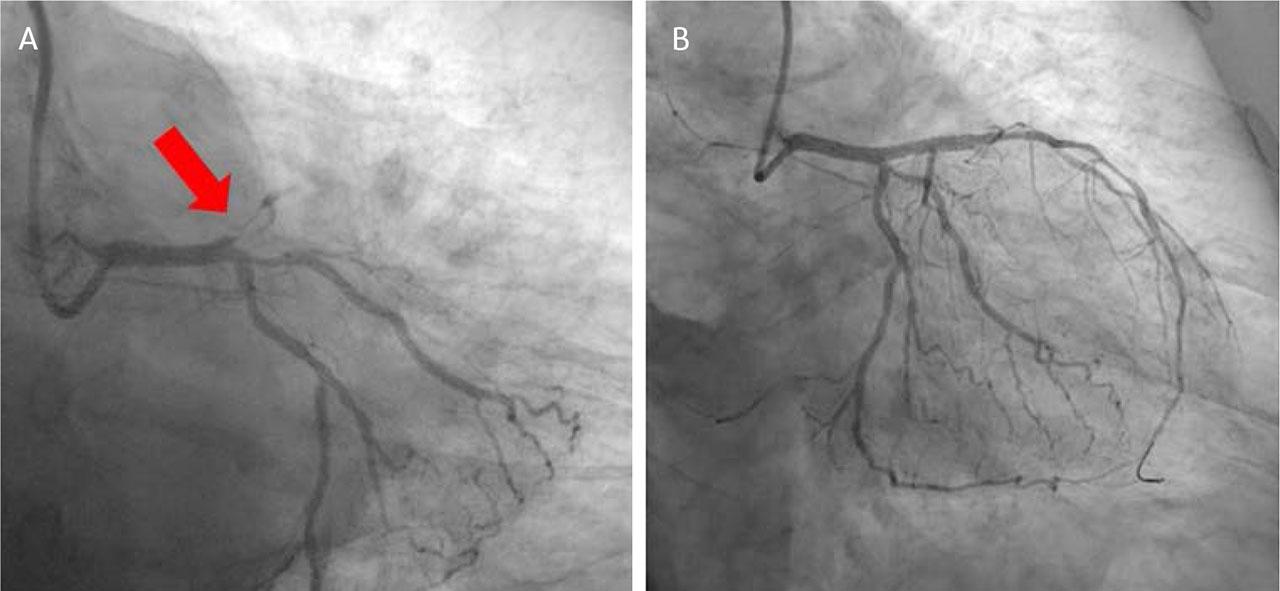

We present the case of a 55-year-old female patient with a history of hypertension and diabetes, admitted to the Cardiology Clinic of the Mureș County Emergency Clinical Hospital for AMI. In accordance with ESC guidelines for AMI, the patient underwent emergency coronary angiography and revascularization, with the implantation of a drug-eluting stent in the left anterior descending artery (Figure 3).

Left coronary artery angiography. A. Acute thrombosis on the left descending anterior artery. B. Post drug eluting stent implantation.